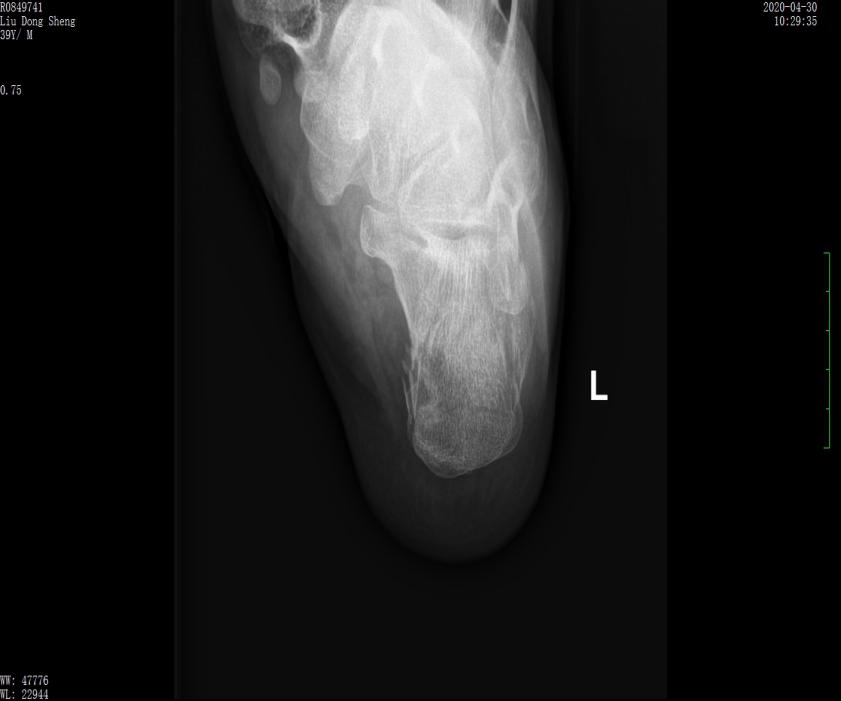

案例1影像

术前X线示跟骨高度丢失,关节面塌陷